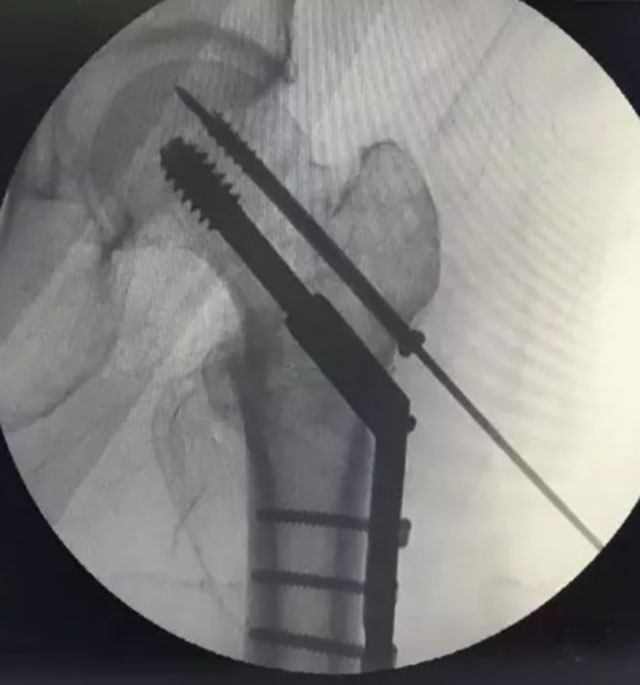

对于年轻患者股骨颈骨折也有新的方案:

①股骨颈骨折FNS内固定:与传统相比抗旋转能力明显提高,可以降低骨折不愈合的几率,提高骨折复位后的稳定性,操作上也比较简单,创伤也比较小,有利于股骨颈骨折患者的术后快速康复,是股骨颈不稳定性骨折的新选择。

股骨颈骨折FNS内固定